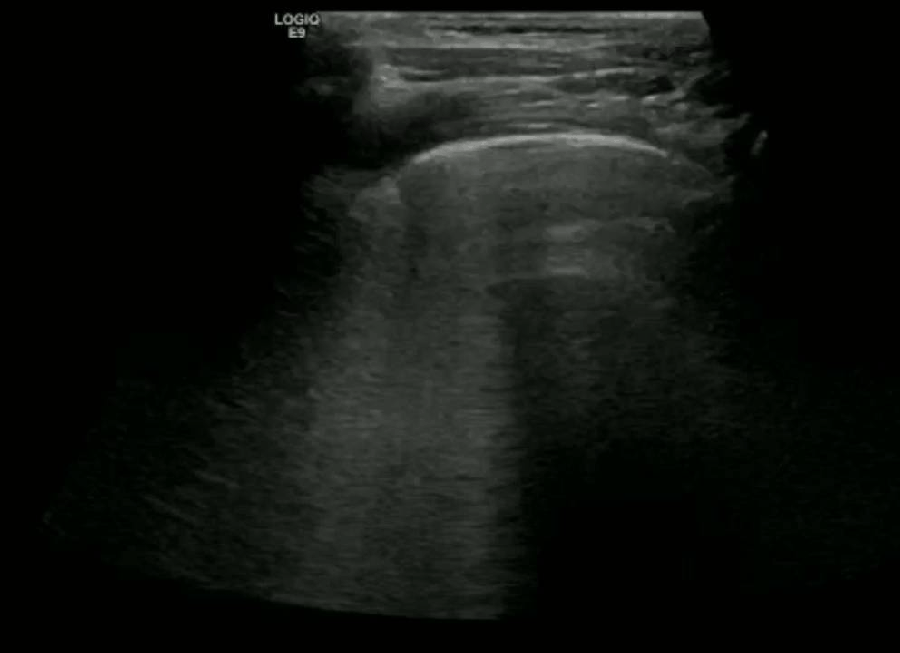

Potential ultrasound findings: (note these are non Covid-19 patients)

Consolidation